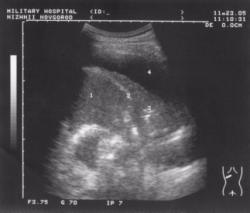

Пациент А., 1936 года рождения. (Рис.1) Находился на лечении в кардиологическом отделении госпиталя с диагнозом: ишемическая болезнь сердца. Сердечная недостаточность. При проведении флюорографического исследования определяется наличие затенений базальных отделов обоих легочных полей справа с косой четкой верхней границей по нижнему краю переднего отрезка V-го ребра, слева по нижнему краю переднего отрезка VI-го ребра.

Заключение: двусторонний экссудативный плеврит.

При проведении ультразвукового исследования плевральных полостей определяется наличие свободной жидкости в обеих плевральных полостях объемом не менее 350-400 мл. Структура жидкости однородная, анэхогенная, без каких либо включений. Отсутствует реакция плевры. В процессе проведения адекватной терапии основного заболевания плевральный выпот быстро регрессировал.